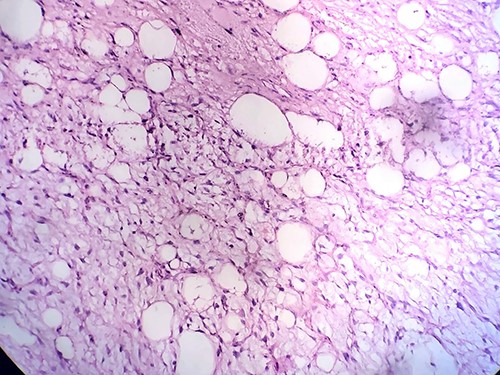

Gross examination revealed large lobulated mass of size 12 cm × 10 cm × 7 cm, weighing 817 g. The cut section showed yellow soft to firm areas with some hemorrhagic areas. Eosin and hematoxylin stain revealed area of lipoblast, pleomorphic cell, mitotic figures with multiple areas of necrosis (Figs 4, 5 and 6). Immunohistochemical reaction showed positivity for S-100 protein, mouse double minute 2 (MDM-2), cyclin-dependent kinase 4 (CDK4) and p16 which helped us differentiate it as dedifferentiated liposarcoma.